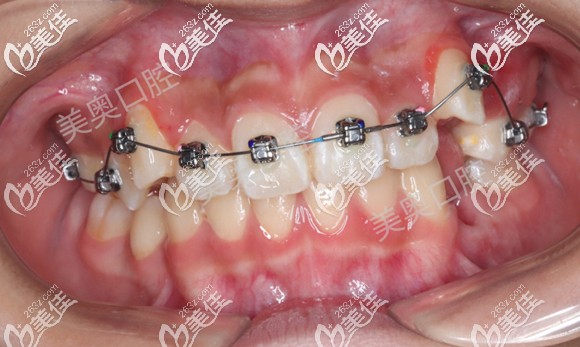

上圖是男孩上牙矯治6個月,下牙矯治4個月的效果,可以看到牙齒明顯有所排齊。